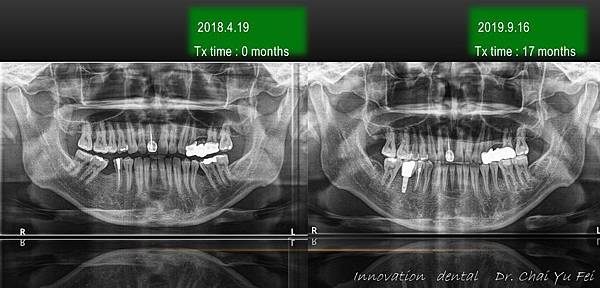

[ 矯正醫師 ] : 展心牙醫 翟聿飛 醫師 [ 植牙醫師 ] : 展心牙醫 王鵬懿 醫師 [ 治療方式 ] : 利用迷你骨釘 , 將傾倒的臼齒扶正,製造空 …